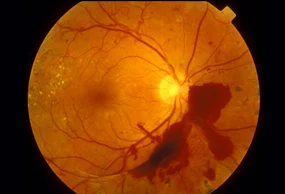

Wet macular degeneration or exudative-

The wet form of macular degeneration accounts for about 10% of all macular degeneration cases. It results from abnormal blood vessels forming and leaking beneath the retina at the back of the eye and causing scarring. Visual loss from this form of macular degeneration can be rapid and severe.